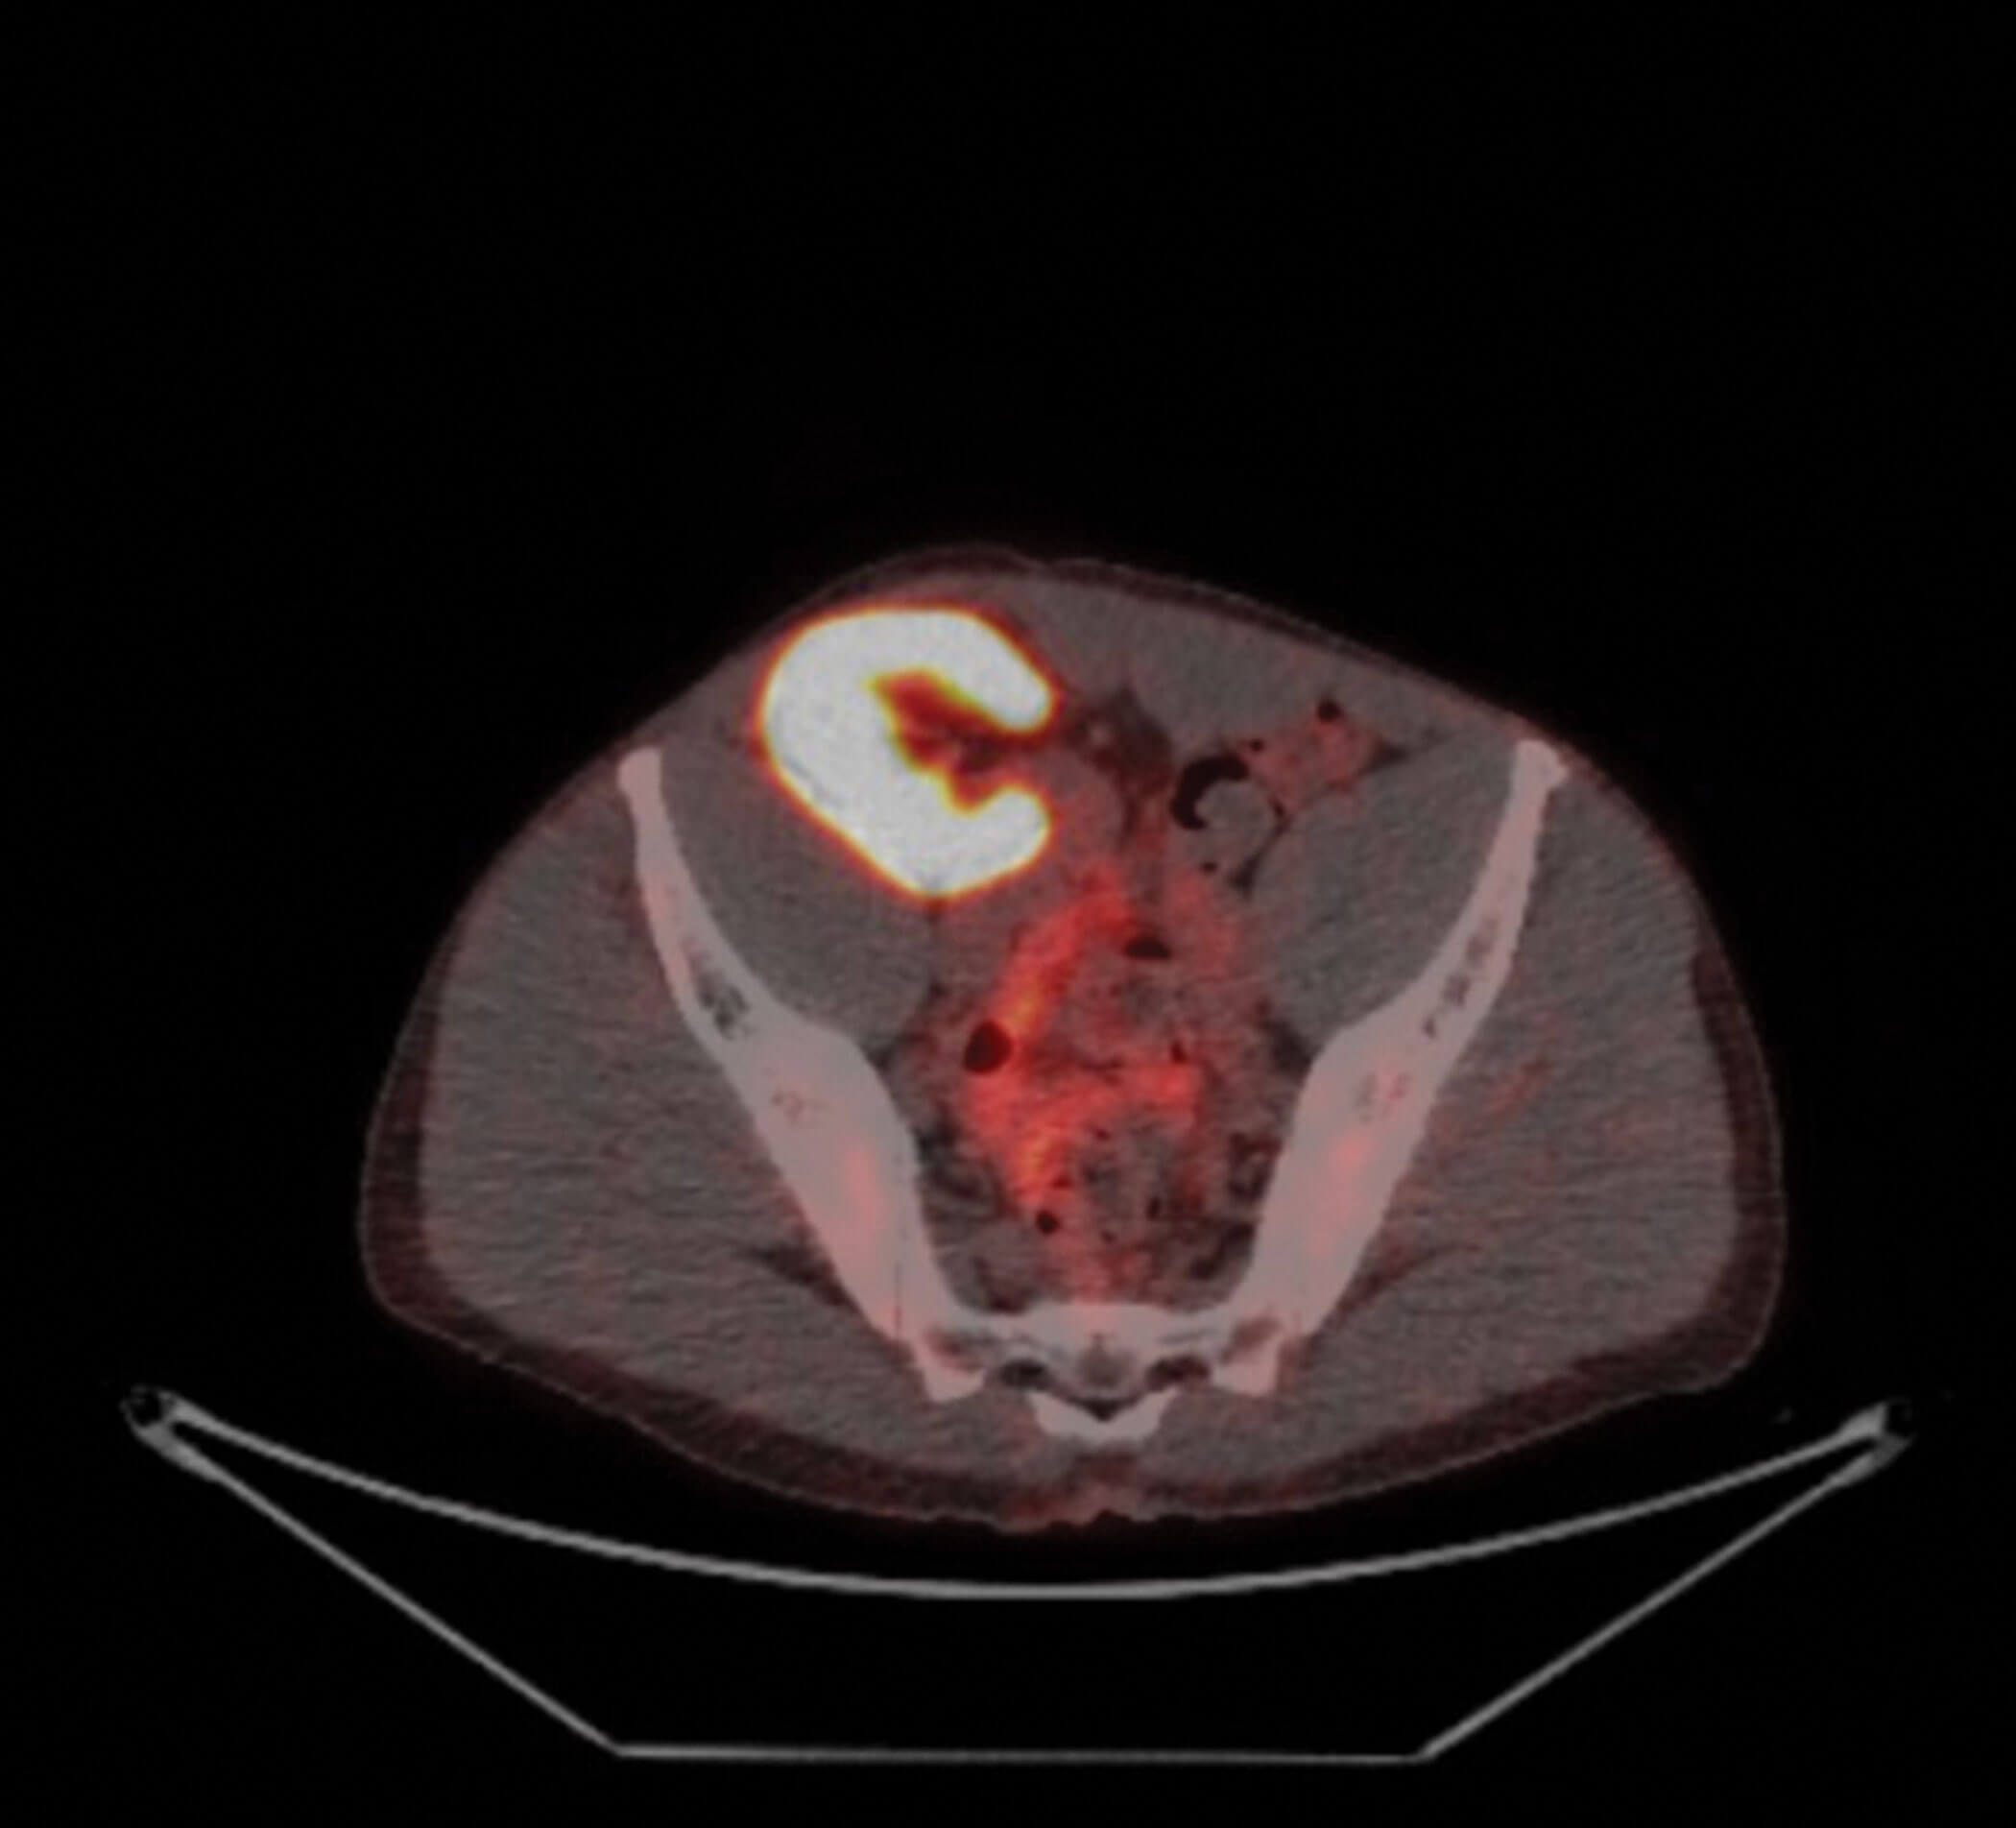

Figure 1: Renal transplant at the level of the iliac crest.

A 55-year-old male had chronic renal failure requiring initial peritoneal dialysis. He had a renal transplant from his partner four years ago. His initial prostate specific antigen (PSA) during the transplant work-up was one. This increased to nine within two years. Another increase in PSA triggered an MRI scan of the prostate which revealed a PI-RADS 5 lesion, T3a in a 20cc prostate. He proceeded to a transperineal prostate biopsy which revealed a Gleason 4+3 cancer with a maximum cancer length of 10mm. Staging prostate specific membrane antigen positron emission tomography (PSMA PET) scan showed no nodal or distant metastasis. He is on regular tacrolimus, anti-hypertensive and insulin. He has a functioning renal transplant.